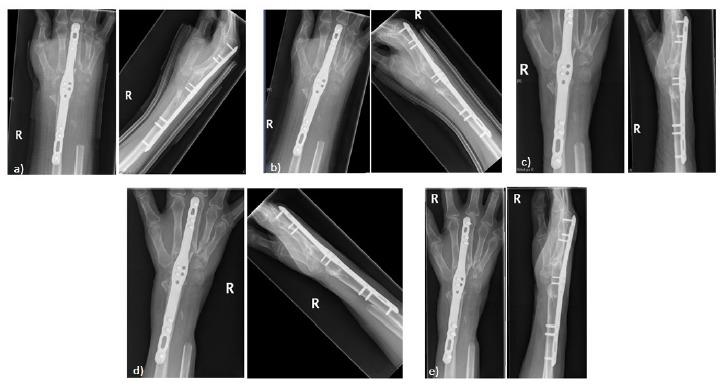

Ulna Autograft for Wrist Arthrodesis: A Novel Approach in Failed Wrist Arthoplasty.

Rheumatoid arthritis is a polyarthropathy affecting approximately 1% of the population worldwide. Wrist involvement is observed around 75% of patients, resulting in substantial disability and morbidity. A multidisciplinary approach to management of such patients is undertaken to prevent disease progression, many go on to develop debilitating disease requiring surgical intervention. Total wrist arthroplasty and arthrodesis are the main options available for those with end-stage disease, with arthroplasty preferred due to its ability to preserve a good degree of wrist function. Where complications occur with total wrist arthroplasty, salvage surgery with arthrodesis can be considered, however this requires satisfactory bone stock to enable stable fusion of the joint following arthroplasty. We report our experience of Ulna strut allografts in wrist arthrodesis in the management of failed total wrist arthroplasty.